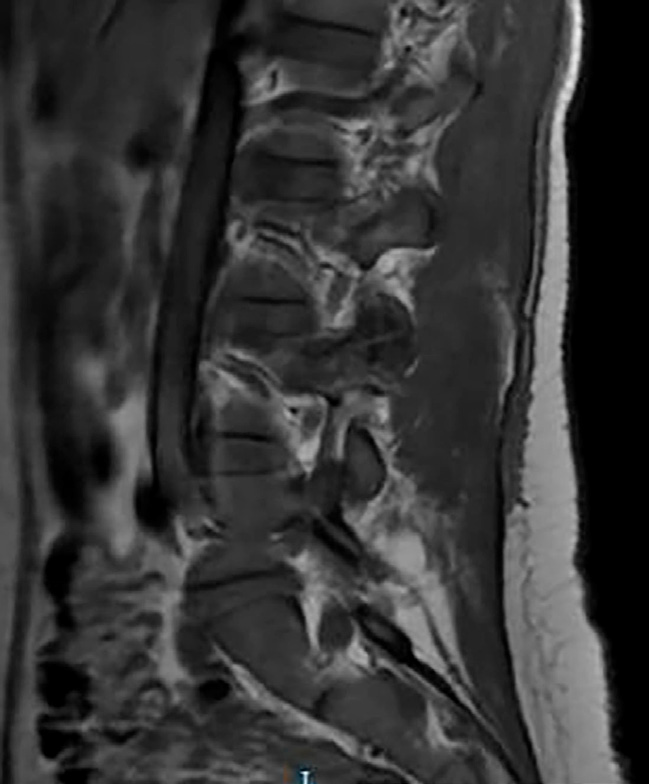

Se procede a realización de TC urgente donde destaca la presencia de contusión pulmonar, sin neumotórax, mínima cantidad de líquido libre periesplénico y fractura del cuerpo vertebral de L4 que involucra a su plataforma articular superior, sin pérdida de altura ni retropulsión hacia el canal medular, con posible foco de hematoma epidural. Adicionalmente, se realiza Rx de la muñeca afecta, donde se observa una fractura-luxación de Galeazzi.

Tras 9 días de ingreso y comentar el caso con el equipo de columna para indicaciones al alta de cara a una IQ definitiva de la muñeca de manera diferida, se decide solicitar una RMN donde se informa una extensión de la fractura hacia los elementos óseos posteriores y disrupción completa del complejo ligamentoso posterior de L3-L4. En base a los nuevos hallazgos, se opta por estabilización de la lesión mediante fusión posterior instrumentada de L4 y L5 con aporte de injerto óseo.

La fractura de chance combinada con lesión ligamentosa es una fractura infrecuente, pero seria, que se puede presentar tras un mecanismo de flexión-distracción al comprometer el cuerpo vertebral en el eje axial. Es fundamental una sospecha precoz, en especial tras dicho mecanismo lesional, ya que hasta el 30% de las lesiones se pasan por alto en la evaluación inicial, incluso tras la realización de un TAC convencional. Adicionalmente, estas lesiones presentan una alta asociación con daños intraabdominales, reportados en hasta el 50% de los casos, lo que denota su importancia. Con todo ello, la RMN es crucial para identificar lesiones del complejo ligamentoso, elemento que determinará el manejo definitivo. En casos con disrupción del citado complejo posterior, como este, está indicada la estabilización quirúrgica para garantizar la estabilidad de la columna y prevenir complicaciones futuras.